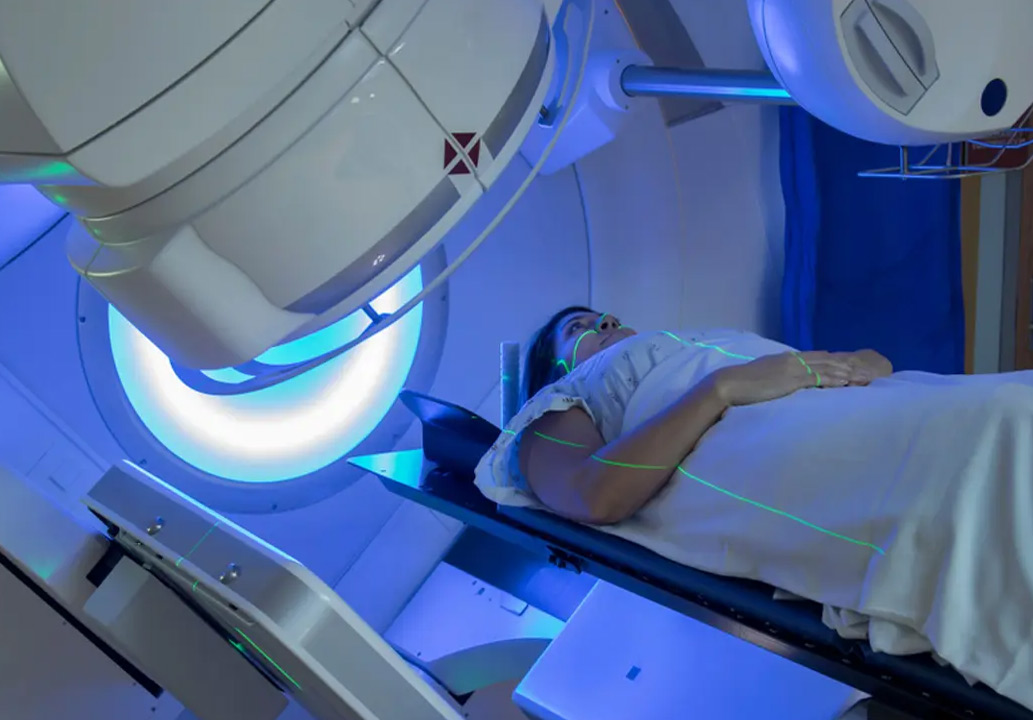

Клиника Ассута занимает лидирующие позиции в области онкоортопедии, применяя инновационные методики и мультидисциплинарный подход к лечению каждого пациента с хондросаркомой. Здесь используются высокоточные технологии система O-arm для контроля и навигации во время органосохраняющей операции, а также технология RapidArc для проведения эффективной лучевой терапии при необходимости. Для реконструкции после удаления новообразования применяют индивидуальные 3D-печатные имплантаты и биологические эндопротезы последнего поколения. Все эти методы в совокупности обеспечивают пациенту наилучший функциональный результат.